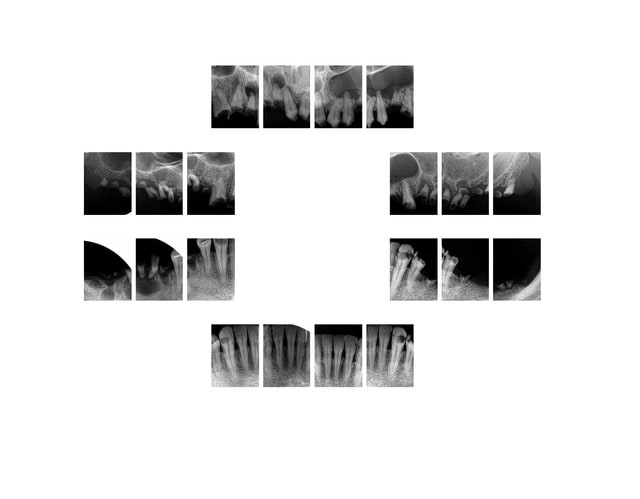

cyber_quenottes

13/10/2014 à 17h18

chicot29 écrivait:

------------------

> Je n'ai meme pas coté un status complet

=================

forcement

ca n'existe plus

par contre là tu as bien 14 à 15 secteurs

soit près de 110 € de clichés

Capture d  cran 2015 03 12 12.28 - Eugenol

Ben si, 10 radios = status. Ceci dit avec le Z 56 il suffisait d'une radio non justifiée pour le foutre par terre.-)))

J'ai compté 8 secteurs. Ici secteur 42 41 32 31 non justifié. Un secteur justifié montre une pathologie, sinon pas justifié. -))))

Bien sur dans les secteurs antérieurs,selon la HAS, jamais les radios ne sont justifiées hors signes d'appels. A l'instant : aucune douleur, ras vous ne trouvez pas. ? -))))